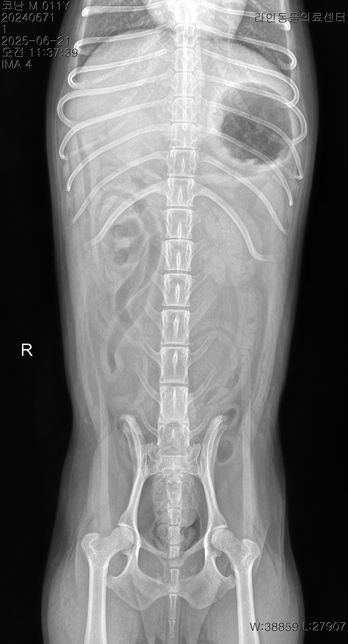

- 반려동물 건강반려동물Q. 강아지 이상증상 이유라도 좀 알고싶습니다..저희 강아지가 어제 아침부터 혀를 내밀고 과호흡에 혀가 보라색이 되고 배가 단단해지길래 바로 응급 병원에 갔더니 별다른 처치는 없었고 산소방에 30분에 있더니 배가 다시 물렁해지며 혀는 여전히 보라색이였으나 엑스레이와 호흡수가 정상이라하여 안정제/진정제 주사를 한대 맞았고 이제 안심을 하고 집에 왓는데 어제 저녁 9시경 애가 물설사와 사진처럼 점액변도 누고 밤 12시경 다시 점액변을 2차례 더 누고 새벽3시경 애가 낑낑거리며 봣더니 배가 다시 단단해져있었고 혀는 괜찮았고 호흡수만 괜찮았지만 하루 종일 잠을 못잤는데 다니던 24시 병원은 전화하니 잘 모르겠다고 솔직한 답변을 주셨고 새벽내내 이리저리 돌아만다녀서 아침에 다른 병원에 가서 엑스레이와 혈액검사 종양검사 등을 하니 저런 결과가 나왔고 이전 병원 엑스레이 사진을 보여드리니 폐침윤이 있어서 다시 엑스레이를 찍어보고 혈액검사도 해보니 심장과 폐문제는 아닌거같다 허리디스크 때문인듯하다 라고 하셨고 복부초음파는 해당 병원 장비가 갑자기 고장이 나서 되지가 않은 그런 상황입니다암은 아니라하고 특이한점은 crp 농도는 정상인데crp 는 13으로 높게 나왔습니다 오늘 찍은 엑스레이상 허리디스크가 심장과 폐 중앙 사이에 있는 허리디스크가 안좋았으며 췌장염은 리파아제 아밀라제가 괜찮다고 아닌거같다고는 하셨는데 cpLi 는 그래서 진행을 안한 상태입니다저도 강아지도 너무 지치는데요 오늘 하루종일 밥을 안먹은 상태이고 주사만 3대 진통제와 스테로이드(쿠싱상관별로없는 약한 스테로이드)를 맞은 상태입니다 대체 어떻게 해야할까요? 정말 허리디스크 때문일까요? 췌장염 가능성은 없을지 여쭤봅니다복부가 단단해지는 증상은 약 3개월전부터있었고 복명음 같은경우도 3개월전부터 있었는데 요즘은 그냥 하루종일 복명음이 들리고 소리도 점점 커지는 느낌입니다.허리디스크라 산책을 하면 안되지만 하도 애가 변을 안누길래 제가 가볍게 산책을 해주면 배가 다시 물렁해지는 그런 상황들이 여러번 있었고 2-3일전부터는 애가 식이알러지 증상도 나타났습니다 고추를 심하게 빨거나 ( 노란 고름이 나와서 항생제도 안에 넣는 세척을 오늘 진행하였고) 평상시에 포비돈으로 희석해서 멸균식염수와 같이 세척해줌에도 작년 9월부터 낫지를 않고 귀와 턱을 미친듯이 긁는 증상들도 있습니다정말 못고쳐도 좋으니 이유만이라도 좀 알고싶은데 병원에 가면 갈수록 저와 강아지는 지쳐만 갑니다한 병원에 계속 다니고 싶어도 첫번째 병원은 엑스레이만 찍고 혈액검사와 복부초음파를 요청하여도 호흡수와 엑스레이가 괜찮다고 그 어떤 처방도 받은것이 없어서 부득이하게 여러 병원들을 다니고 있는 상황인데 병원들이 가깝지도 않아서 차로 최소 1시간 거리들인 상황이라 정말 상상 이상으로 지치는데부디 혈액검사와 증상들을 살펴봐주시고 짐작이 가는 질병이나 췌장이나 대장쪽 문제는 없는지 알고싶습니다정장제와 허리디스크 약을 처방받은 상황이며 일주일동안 약을 먹어보고 그래도 이상하면 췌장이라고 들었습니다 참고로 아밀라아제 리파아제가 정상수치여도 초음파상 췌장에 에코가 있었던 이력이 있으며 심장 같은 경우는 b1 이라고 하고 청진도 잘 안들이기에 여러 병원들이 b2 는 아니라하였고 오늘 찍은 엑스레이에선 폐침윤은 없었습니다 다만 쿠싱이 살짝 의심은 된다고는 하였습니다 멏개월전에는 쿠싱검사시 cor 이 (1-6 이 정상인데 ) 인지 9 정도 나왔는데 몇개월후 오늘은 7.5 로 되었습니다 • T4-6 vertebrae의Rt. caudal articular process의defect 확인됩니다. (→)• T13-L1 vertebrae의IVDS(intervertebral disc space)가주변에비해좁게확인됩니다.(→• T13-L1 vertebrae의IVDS가주변에비해좁게확인되어IVDD 가능성고려됩니다. 신경계검사등추가적인신체검사추천되며, 신체검사상특이소견또는임상증상확인될경우척수실질평가를위한MRI 검사가추천될수있습니다.• T4-6 vertebrae의Rt. caudal articular process의dysplasia 확인되며, congenitalanomaly로고려됩니다. 이는, incidental finding으로고려되나, 척추의불안정성을야기하여IVDD를유발할수있습니다마지막 사진은 저희 강아지 작년 ct 촬영 사진입니다